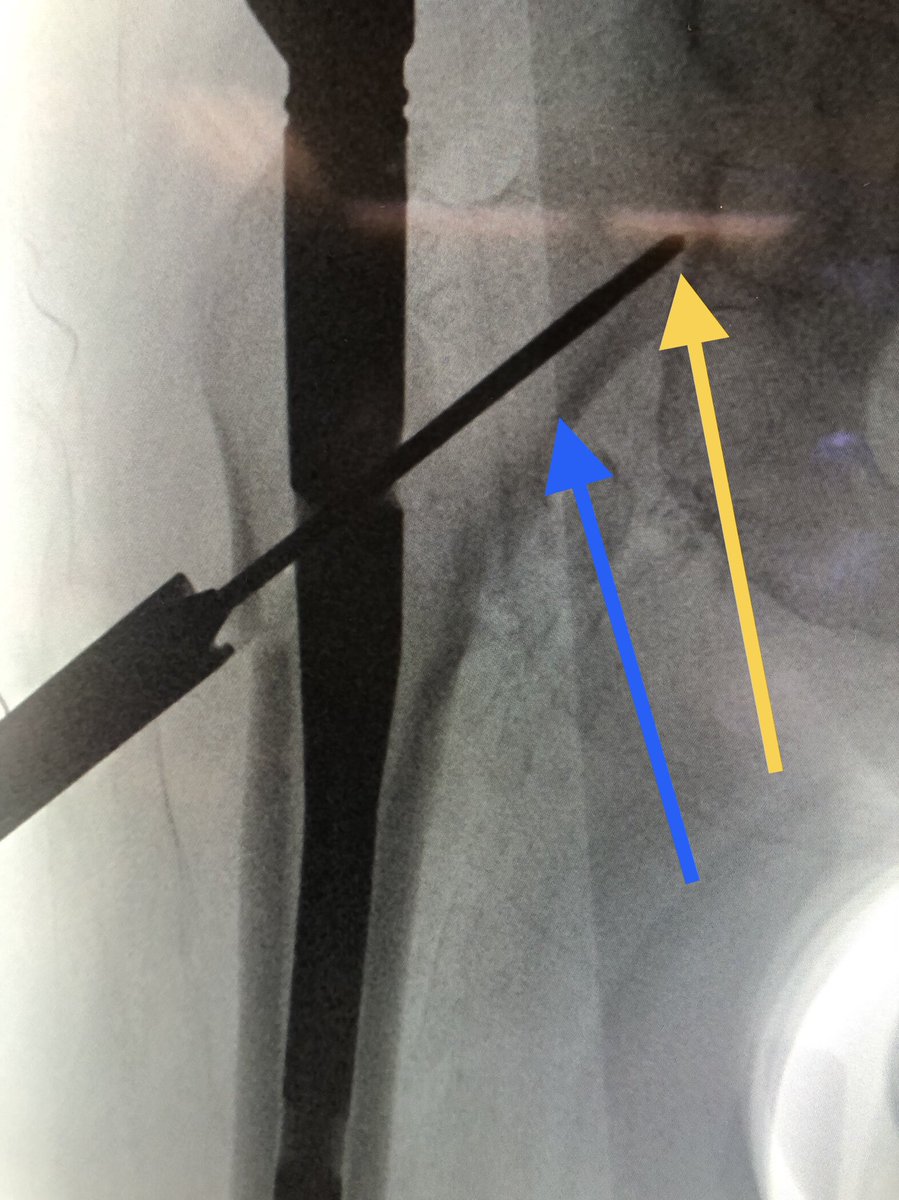

[14/18] If you line up screw handle with the line of the femur (blue) your screw end will be in the right plane. If it’s a left hip (clockwise screwing can flex the proximal fragment) I also build in an extra turn to derotate the proximal fragment if needed.